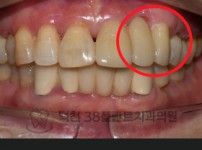

치료전후